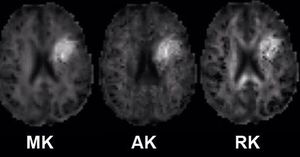

Diffusion Kurtosis Imaging (DKI) is a method for quantifying the degree to which water diffusion in biological tissues is non Gaussian. Since tissue structure is responsible for the deviation of water diffusion from the Gaussian behavior typically observed in homogeneous solutions, this method provides a specific measure of tissue structure, such as cellular compartments and membranes. We can distinguish the anisotropic Gaussian distribution with an extend form of DTI. DKI protocols differ from DTI protocols in requiring at least 3 b-values (as compared to 2 b-values for DTI) and at least 15 independent diffusion gradient directions (as compared to 6 for DTI). Typical protocols for brain have b-values of 0, 1000, 2000 s/mm2 (the higher b value the better as long as you have adequate SNR) with 30 diffusion directions. Image post-processing requires the use of specialized algorithms which can generate a set of kurtosis (mean, axial, radial) parametric maps.